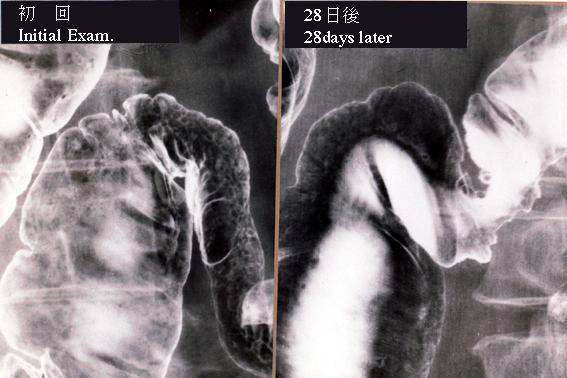

直肠癌术后5年所见的狭窄性的缺血性大肠炎

炎症性・溃疡性疾患/缺血性大肠炎

大肠/横结肠

X线